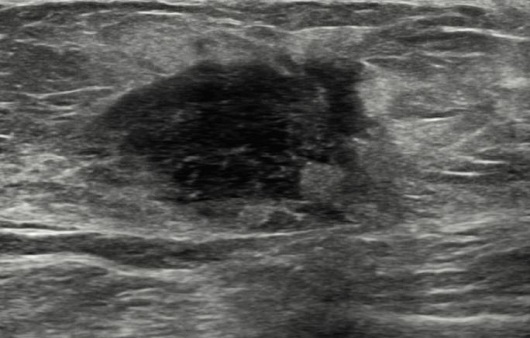

유방암 초기증상 - 덩어리 또는 멍울

유방암을 알아차리는 가장 일반적인 방법은 유방에 덩어리 또는 만져지는 덩어리가 만져지는 것입니다. 멍울은 이전에 본 적 없는 신비한 덩어리이며, 악성이라면 단단하고 고정되어 움직이지 않으며 모양이 불규칙합니다. 모든 멍울이 악성은 아니며 양성일 수도 있으므로 의사와 정기적으로 검진을 받는 것이 중요하므로 이러한 유방암 초기증상을 그냥 지나치지 마시기 바랍니다.